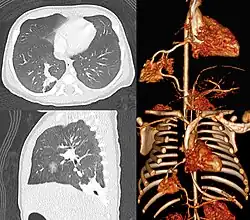

Pulmonale Sequester sind Lungenfehlbildungen. Die funktionslosen Lungenabschnitte gehören zwar ontogenetisch zur Lunge, sind aber eigenständig mit Blut versorgt. Pulmonale Sequester können Ausgangspunkt für rezidivierende Infektionen sein.

Schätzungsweise ein bis sechs Prozent aller angeborenen Lungenfehlbildungen machen das pulmonale Sequester aus, es handelt sich also um eine äußerst seltene Erkrankung.[1] Sie entwickeln sich aus überzähligen Lungenknospen in der Embryogenese. Primär besteht keine Verbindung zum Bronchialsystem. Am häufigsten finden sich pulmonale Sequester im Bereich des linken Lungenunterlappens, sonst meist im rechten posterioren Unterlappensegment.[2] Die arterielle Blutversorgung erfolgt über die Aorta thoracica, der Abfluss über die Lungenvenen (intralobulärer Sequester). Bei einem entsprechend großen Volumen der zuführenden Gefäße kann es so zu einem kreislaufrelevanten Shunt kommen.

Extralobuläre Sequester manifestieren sich meist im 1. Lebensjahr. Sie haben eine eigene Pleura und verursachen oft rezidivierende Pneumonien. Intralobuläre Sequester manifestieren sich meist nach dem 20. Lebensjahr. Sie haben keine eigene Pleura und enthalten oft Schleimpfröpfe. Die Diagnosestellung erfordert meist eine Angiographie.